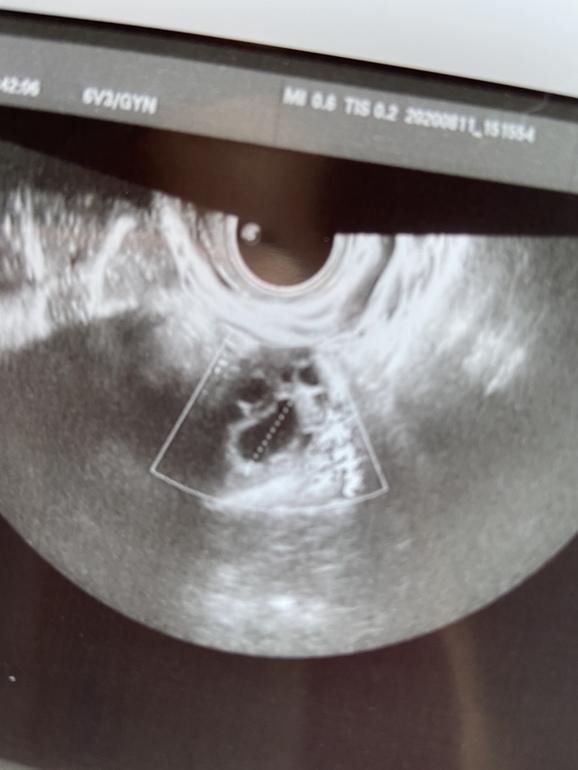

Я сходила сегодня вот сравнение

Будет сравнение узи от субботы и сегодня

Суббота - в левом образование 8 мм

Сегодня - в левом образование 17.2 мм

Суббота в правом образование 10 мм

Сегодня в правом образование 14 мм

Эндометрий суббота 11 мм

Сегодня 11.4 мм

В правом есть что то похожее на кровоток

Почему нет кольцевого кровотока???

Сейчас 4 день после предполагаемой О

Говорят что эти 2 образование - спасшиеся фолликулы которые слвулировали

В заклбчении овуляция в двух яичниках

Фото ЖТ прилагаю

Похоже ли на ЖТ по фото???